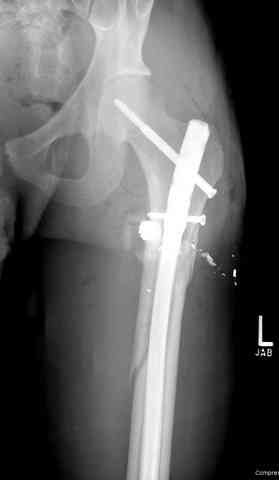

3 сегментарный перелом бедра с переломом Хоффа фрагментом, сделано из минимального доступа

Для фиксации огнестрельных переломов бедра и длинных костей предпочтение отдаем интрамедуллярному методу фиксации, о котором еще в 1993 году написали Bergman M. Tornetta P. Kerina M. Sandhu H. Simon G. Deysine G. Journal of Trauma. [JC:kaf] 34(6):783-5

В наших условиях рекомендуемые коллегами линейные наружные фиксаторы из-за недостаточной стабильности как окончательная фиксация применяется крайне редко. В основном наружный фиксатор применяем как временный с дальнейшим переходом на традиционный метод фиксации. Выбор времени фиксации зависит от общего состояния или от улучшения мягкотканого покрытия.